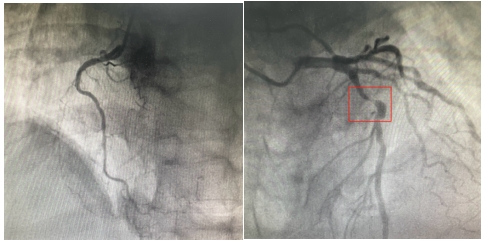

23:38分

导丝通过病变血管,打通血管。从患者到达导管室门口至导丝通过(简称D2W),门丝时间仅用时13分钟!

23:43分

于前降支近至中段、病变处植入支架2枚,手术治疗完成。

血管开通后